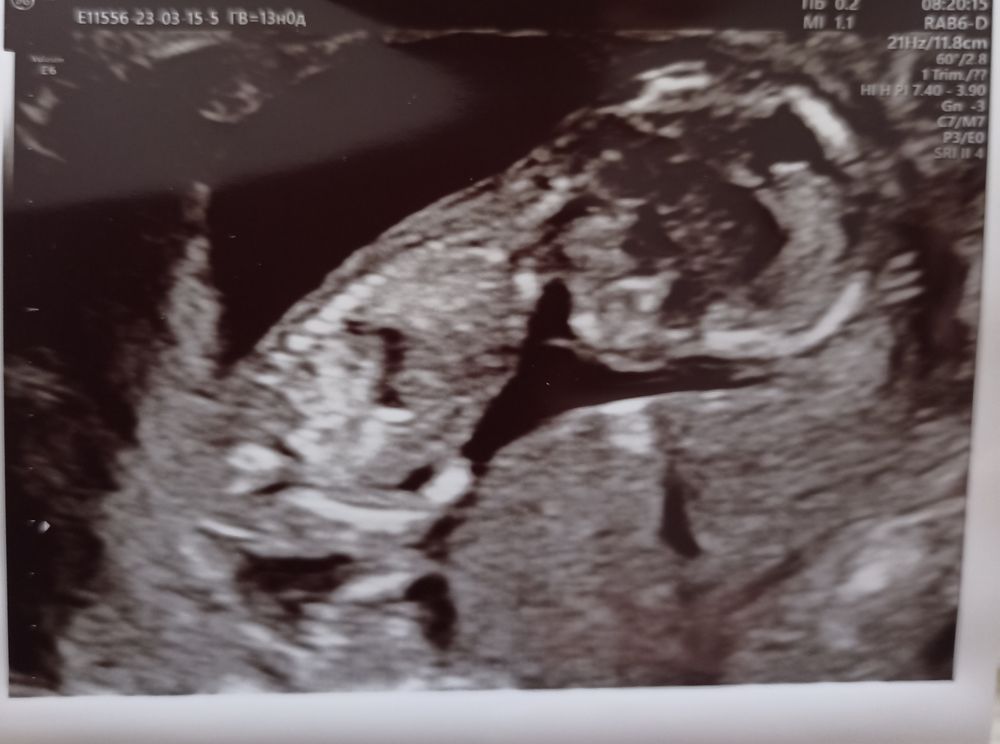

Первый скрининг! 13 недель.

Какое это счастье! Эмоции мои словами не описать!!!! Мы прошли первый УЗИ- скрининг!!!!! Мой малыш!!! Он такой уже большой! Крутился, вертелся,ручками личико закрывал!!!! Мой маленький ангелочек!!!!! По узи все хорошо. Кровь сдала, результат чуть позже. Девочки!!!! Всем, всем желаю таких счастливых эмоций!!!!!!! Всё у нас у всех будет хорошо!!!!!!!!!!!